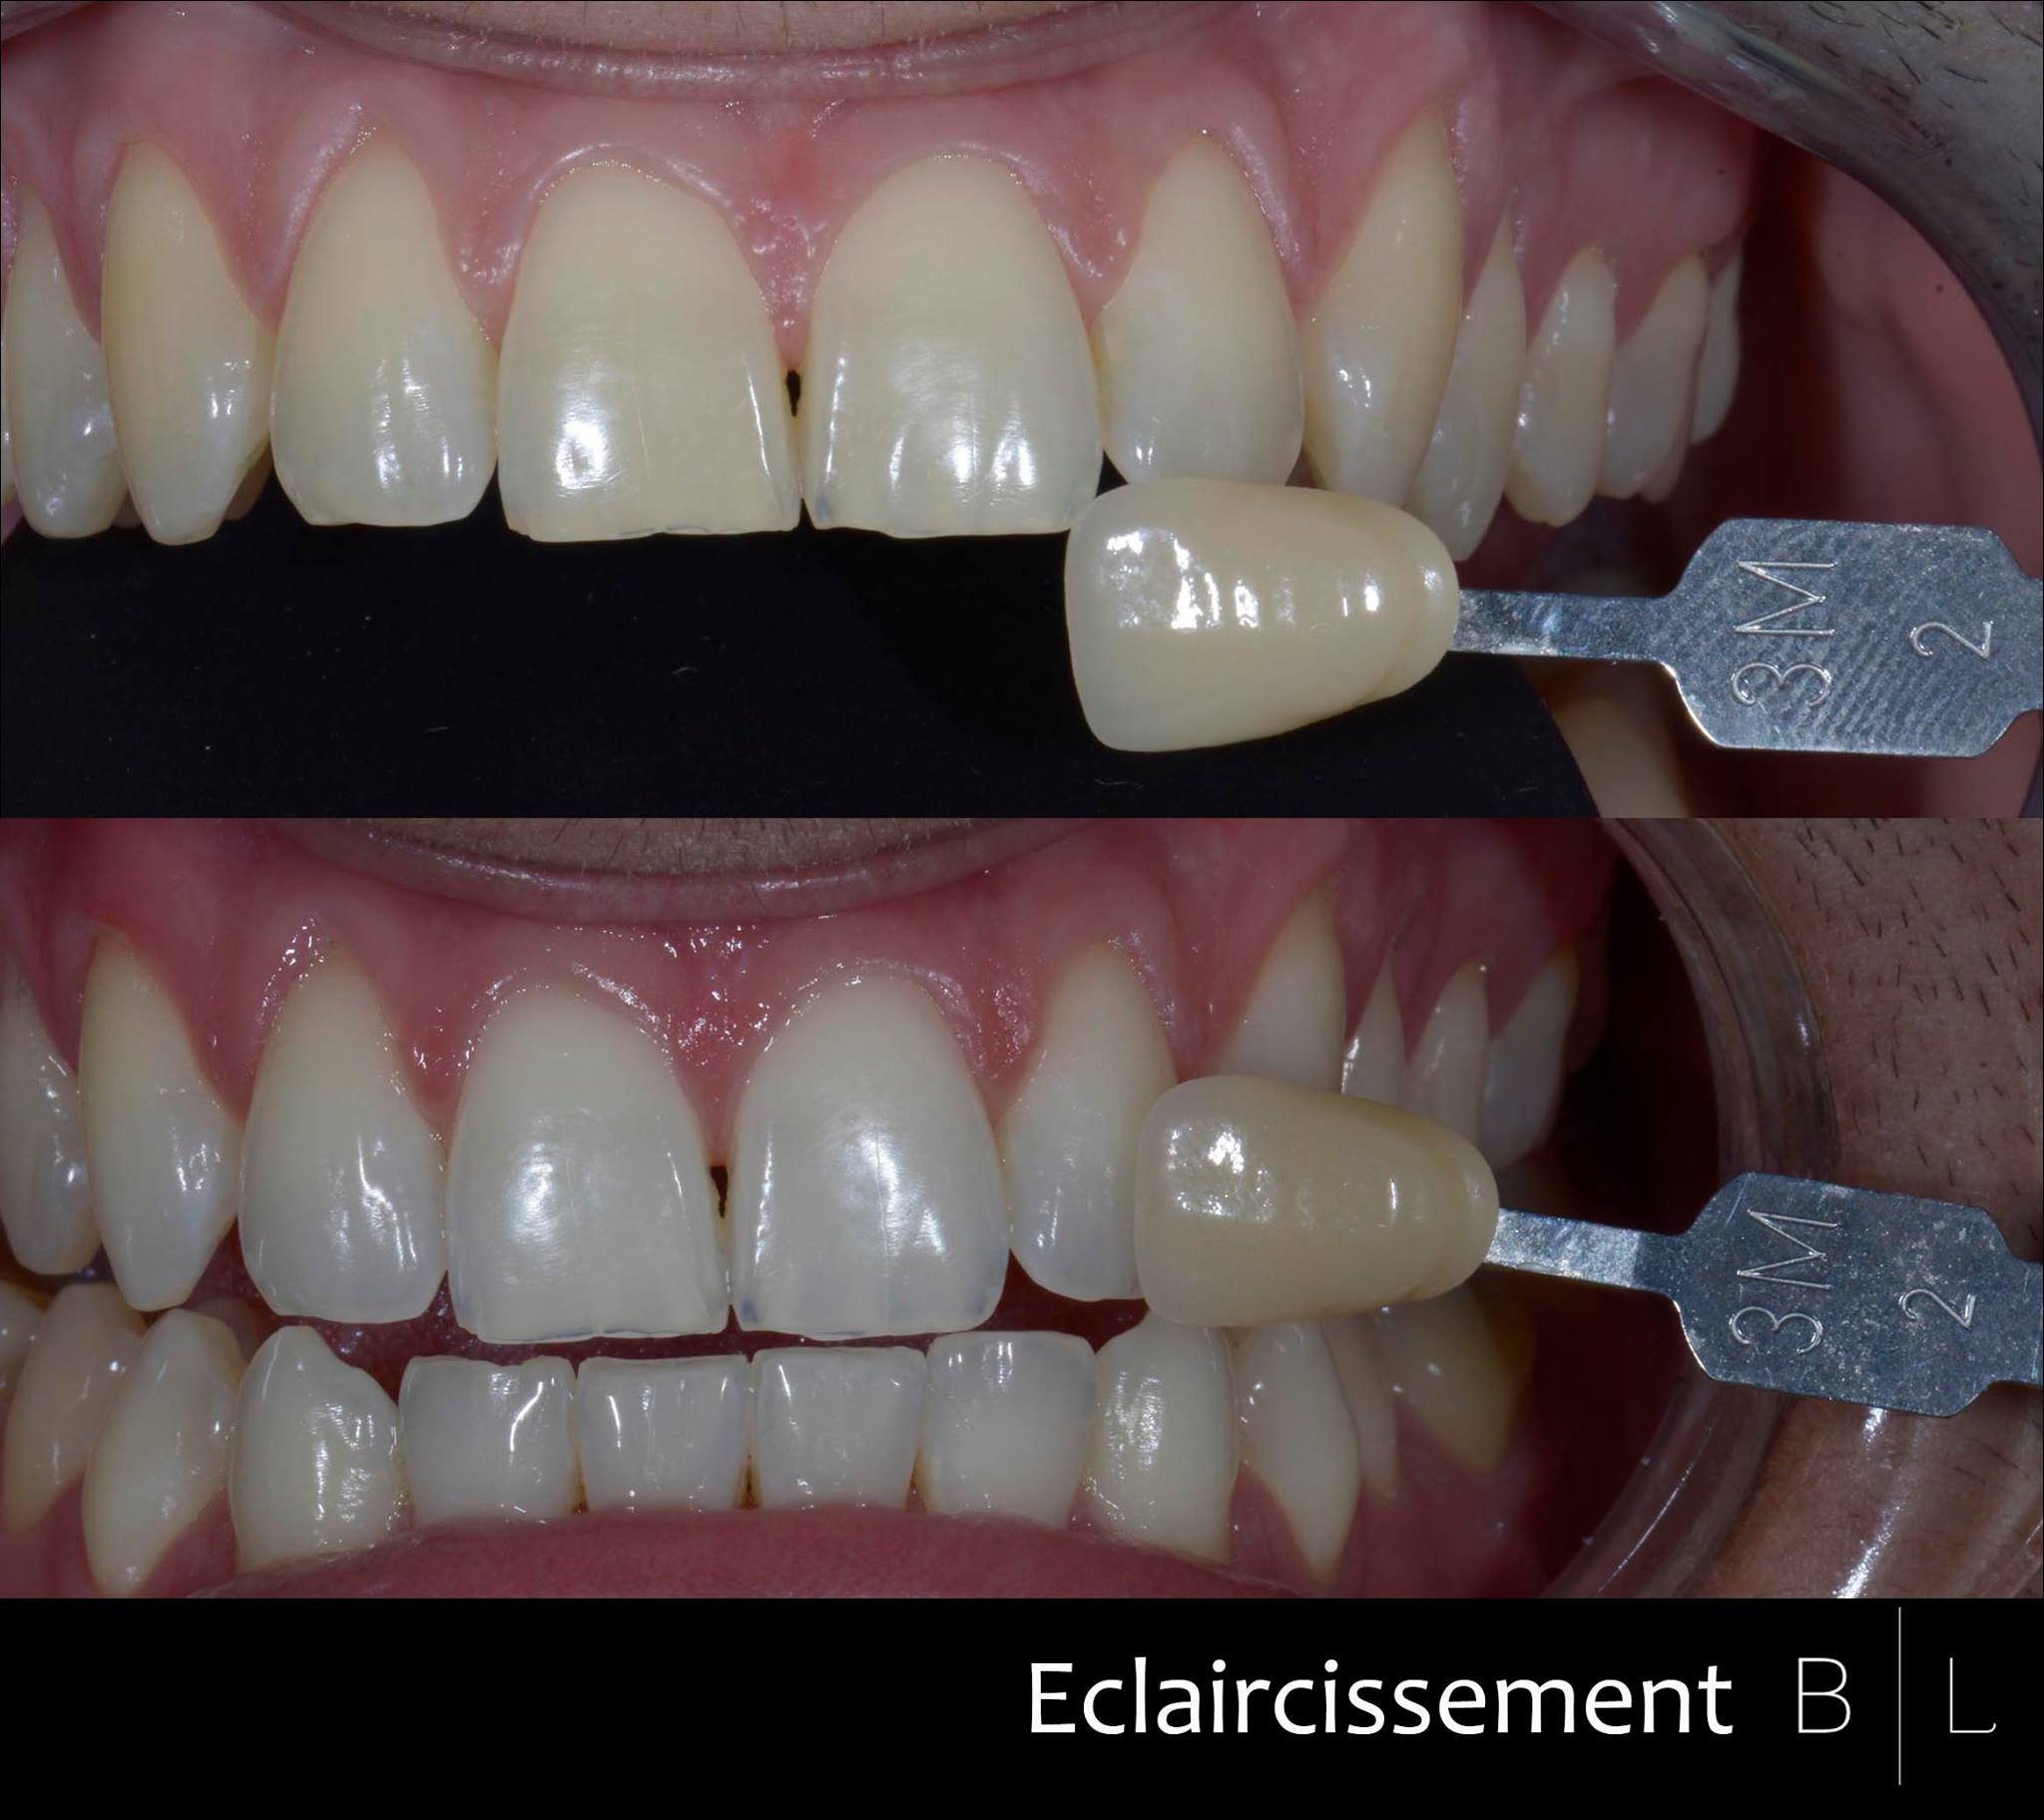

Blanchiment dentaire.

Blanchiment dentaire.

Blanchiment + Facettes